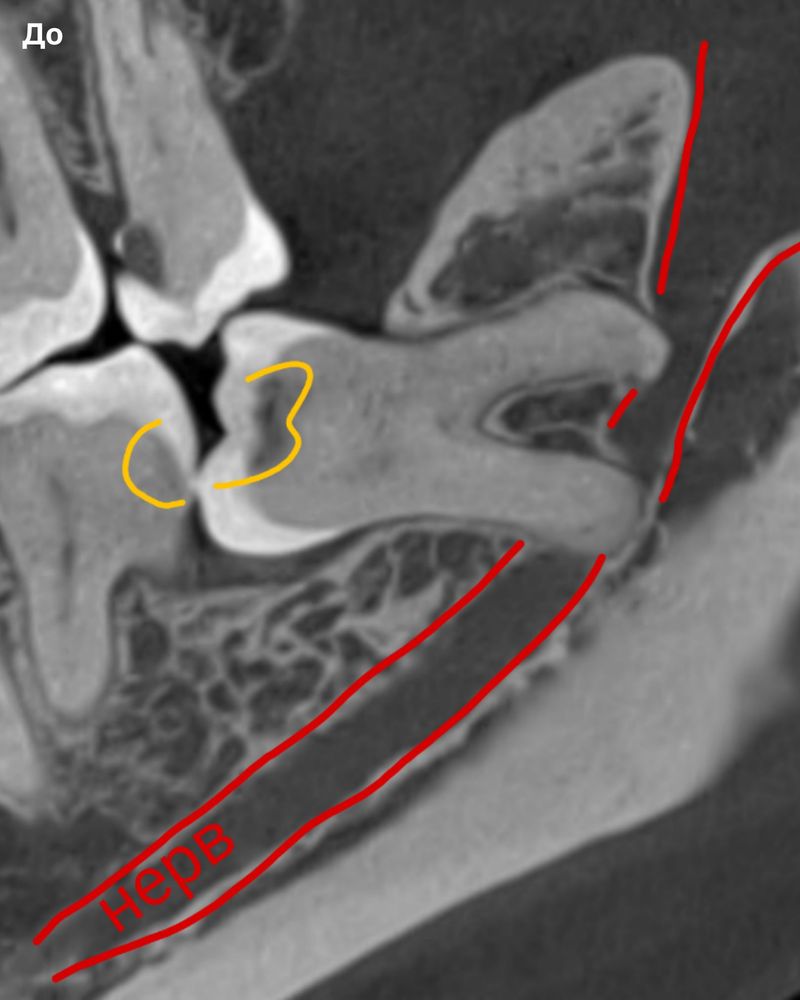

Сложный зуб мудрости и как мы его удалили без риска для нерва

Пациент пришел к нам со сложным нижним зубом мудрости, который прорезался только частично, занимал неправильное положение и упирался коронкой в корень соседней семерки. Из-за постоянного скопления пищи на обоих зубах развился глубокий кариес, появились боли, и откладывать удаление больше нельзя было.

Зуб лежал горизонтально и имел три корня, что встречается крайне редко. Корни не только обнимали мандибулярный канал с нервом, но и продавливали его, поэтому операция несла повышенные риски. В таких случаях возможны осложнения со стороны нерва — онемение угла рта и подбородка или сильная боль.